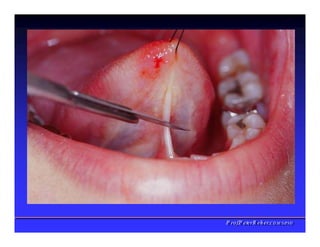

Assoalho da Boca